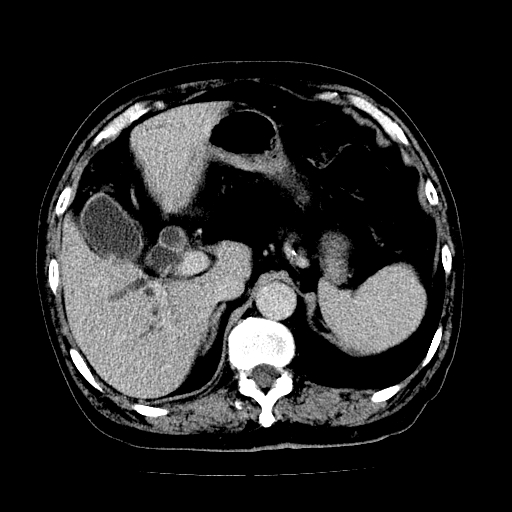

男,71岁,皮肤黄染四天。

肝内外胆管及胆总管上段扩张,考虑为梗阻所致,建议mrcp检查。

考虑胆总管癌并肝内外胆管扩张。

胆管癌并肝内外胆管扩张。

支持考虑胆总管癌并肝内外胆管扩张。 局部应薄扫。心包钙化。

胰腺上端胆总管内见软组织影,强化不明显,结合临床,还是考虑低位梗阻性黄疸,胆总管癌可能性大